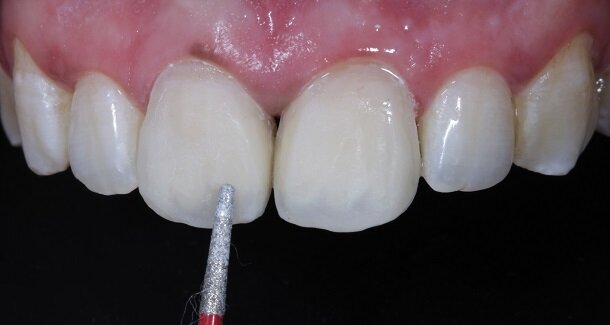

Fig 12- Gross finishing for the outline of the tooth was achieved using Red ring (composite finishing) tapered rounded bur. Almost 80% of the finishing can be done using this bur. It also helps in creating surface macro and micro anatomical variations. For better control, this bur can be used on a contra-angled hand-piece along with a convertor.

Fig 13 and 14 -Transitional Line angles were marked using a pencil and made prominent using medium grit 3M Soflex Discs proximally. The apparent faces of both the teeth were thus, created.

Fig 15 and 16 - For the surface texture; vertical surface macro-anatomy showing developmental grooves (mesial and distal) were marked using a pencil and created using the red ring finishing bur.

Fig 17- Horizontal surface micro-anatomy, that is, the Perikymata or imbrication lines were marked cervically and incisally, using a pencil and created using the red ring finishing bur.